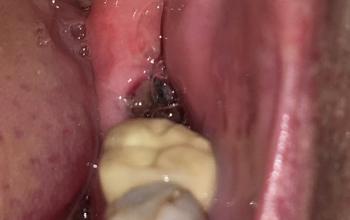

✅ Emergency Dental Services

– Toothaches

– Broken or chipped teeth

– Swelling and infections